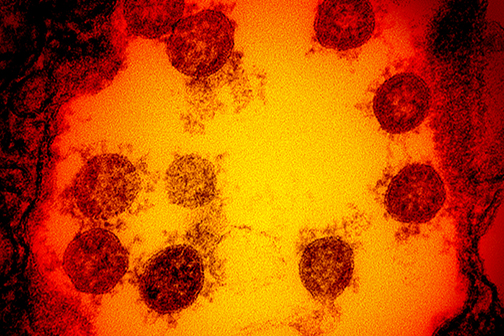

LSU Health New Orleans Research Quantifies Effect of Chronic Diseases on Racial Disparity in COVID-Associated Hospitalizations

LSU Health New Orleans conducted the first research using disease surveillance data to quantify the effect of chronic diseases on racial disparity in COVID-associated hospitalizations. The research team, led by Xiao-Cheng Wu, MD, MPH, Professor and Director of the Louisiana Tumor Registry at LSU Health New Orleans School of Public Health, reports that chronic diseases explained almost two-fifths of the racial disparity in COVID-associated hospitalizations among cancer patients, specifically common chronic diseases such as hypertension, diabetes and chronic kidney disease. More

LSU Health New Orleans Precision Medicine Lab Finds New Omicron Subvariants

LSU Health New Orleans’ Precision Medicine Lab has found two new SARS-CoV-2 variants in Louisiana. BE.1 and BF.1 are subvariants of the Omicron Variant of Concern that has driven the latest surge. The Lab identified three cases of BE.1 and one case of BF.1 in tests performed at the end of June. More

LSU Health New Orleans Precision Medicine Lab Finds Omicron Variant

Among the 567 new COVID-19 cases reported today in Louisiana are two confirmed cases of the Omicron variant from the New Orleans area found by the LSU Health New Orleans’ Precision Medicine Laboratory. Directed by Lucio Miele, MD, PhD, Professor and Chair of Genetics at LSU Health New Orleans School of Medicine, along with Dr. Gordon Love, Professor and Chair of Pathology, the lab sequences samples from positive tests to learn what strains of the virus that causes COVID-19 are infecting patients here. More

LSU Health New Orleans Study Reports Compound Blocks SARS-CoV-2 and Protects Lung Cells

Research conducted at LSU Health New Orleans Neuroscience Center of Excellence reports that Elovanoids, bioactive chemical messengers made from omega-3 very-long-chain polyunsaturated fatty acids discovered by the Bazan lab in 2017, may block the virus that causes COVID-19 from entering cells and protect the air cells (alveoli) of the lung. More